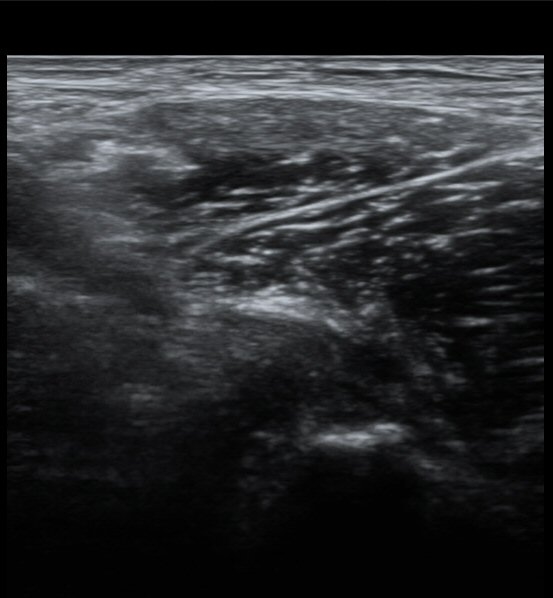

ŽÃËÀÚ¸¦ Á¶±Ý ³»ÃøÀ¸·Î À̵¿ÇÏ´Ï ÈûÁÙÀÇ °í¿¡ÄÚ°¡ ¼Ò½ÇµÇ¾î º¸ÀδÙ(»çÁø 2, 3)